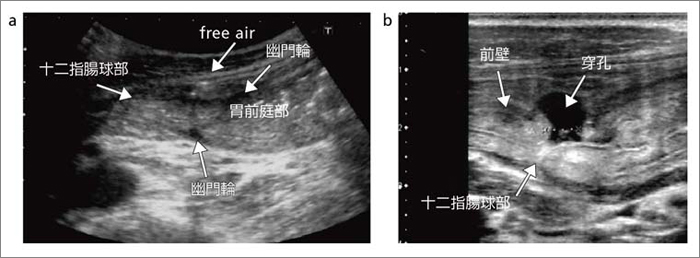

もらって嬉しい出産祝い 消化器内科 第28号(Vol.4 No.3,2022)特集:体外式超音波による 医学一般

消化器内科 第28号(Vol.4 No.3,2022)特集:体外式超音波による,

消化器内科 第28号(Vol.4 No.3,2022)特集:体外式超音波による, 消化管エコーの最新動向 - 新。超音波診断 Vol.03 - 東芝,

消化管エコーの最新動向 - 新。超音波診断 Vol.03 - 東芝, 腹部超音波検査(腹部エコー検査) | 医療法人 木村医院,

腹部超音波検査(腹部エコー検査) | 医療法人 木村医院, 消化管エコーの最新動向 - 新。超音波診断 Vol.03 - 東芝,